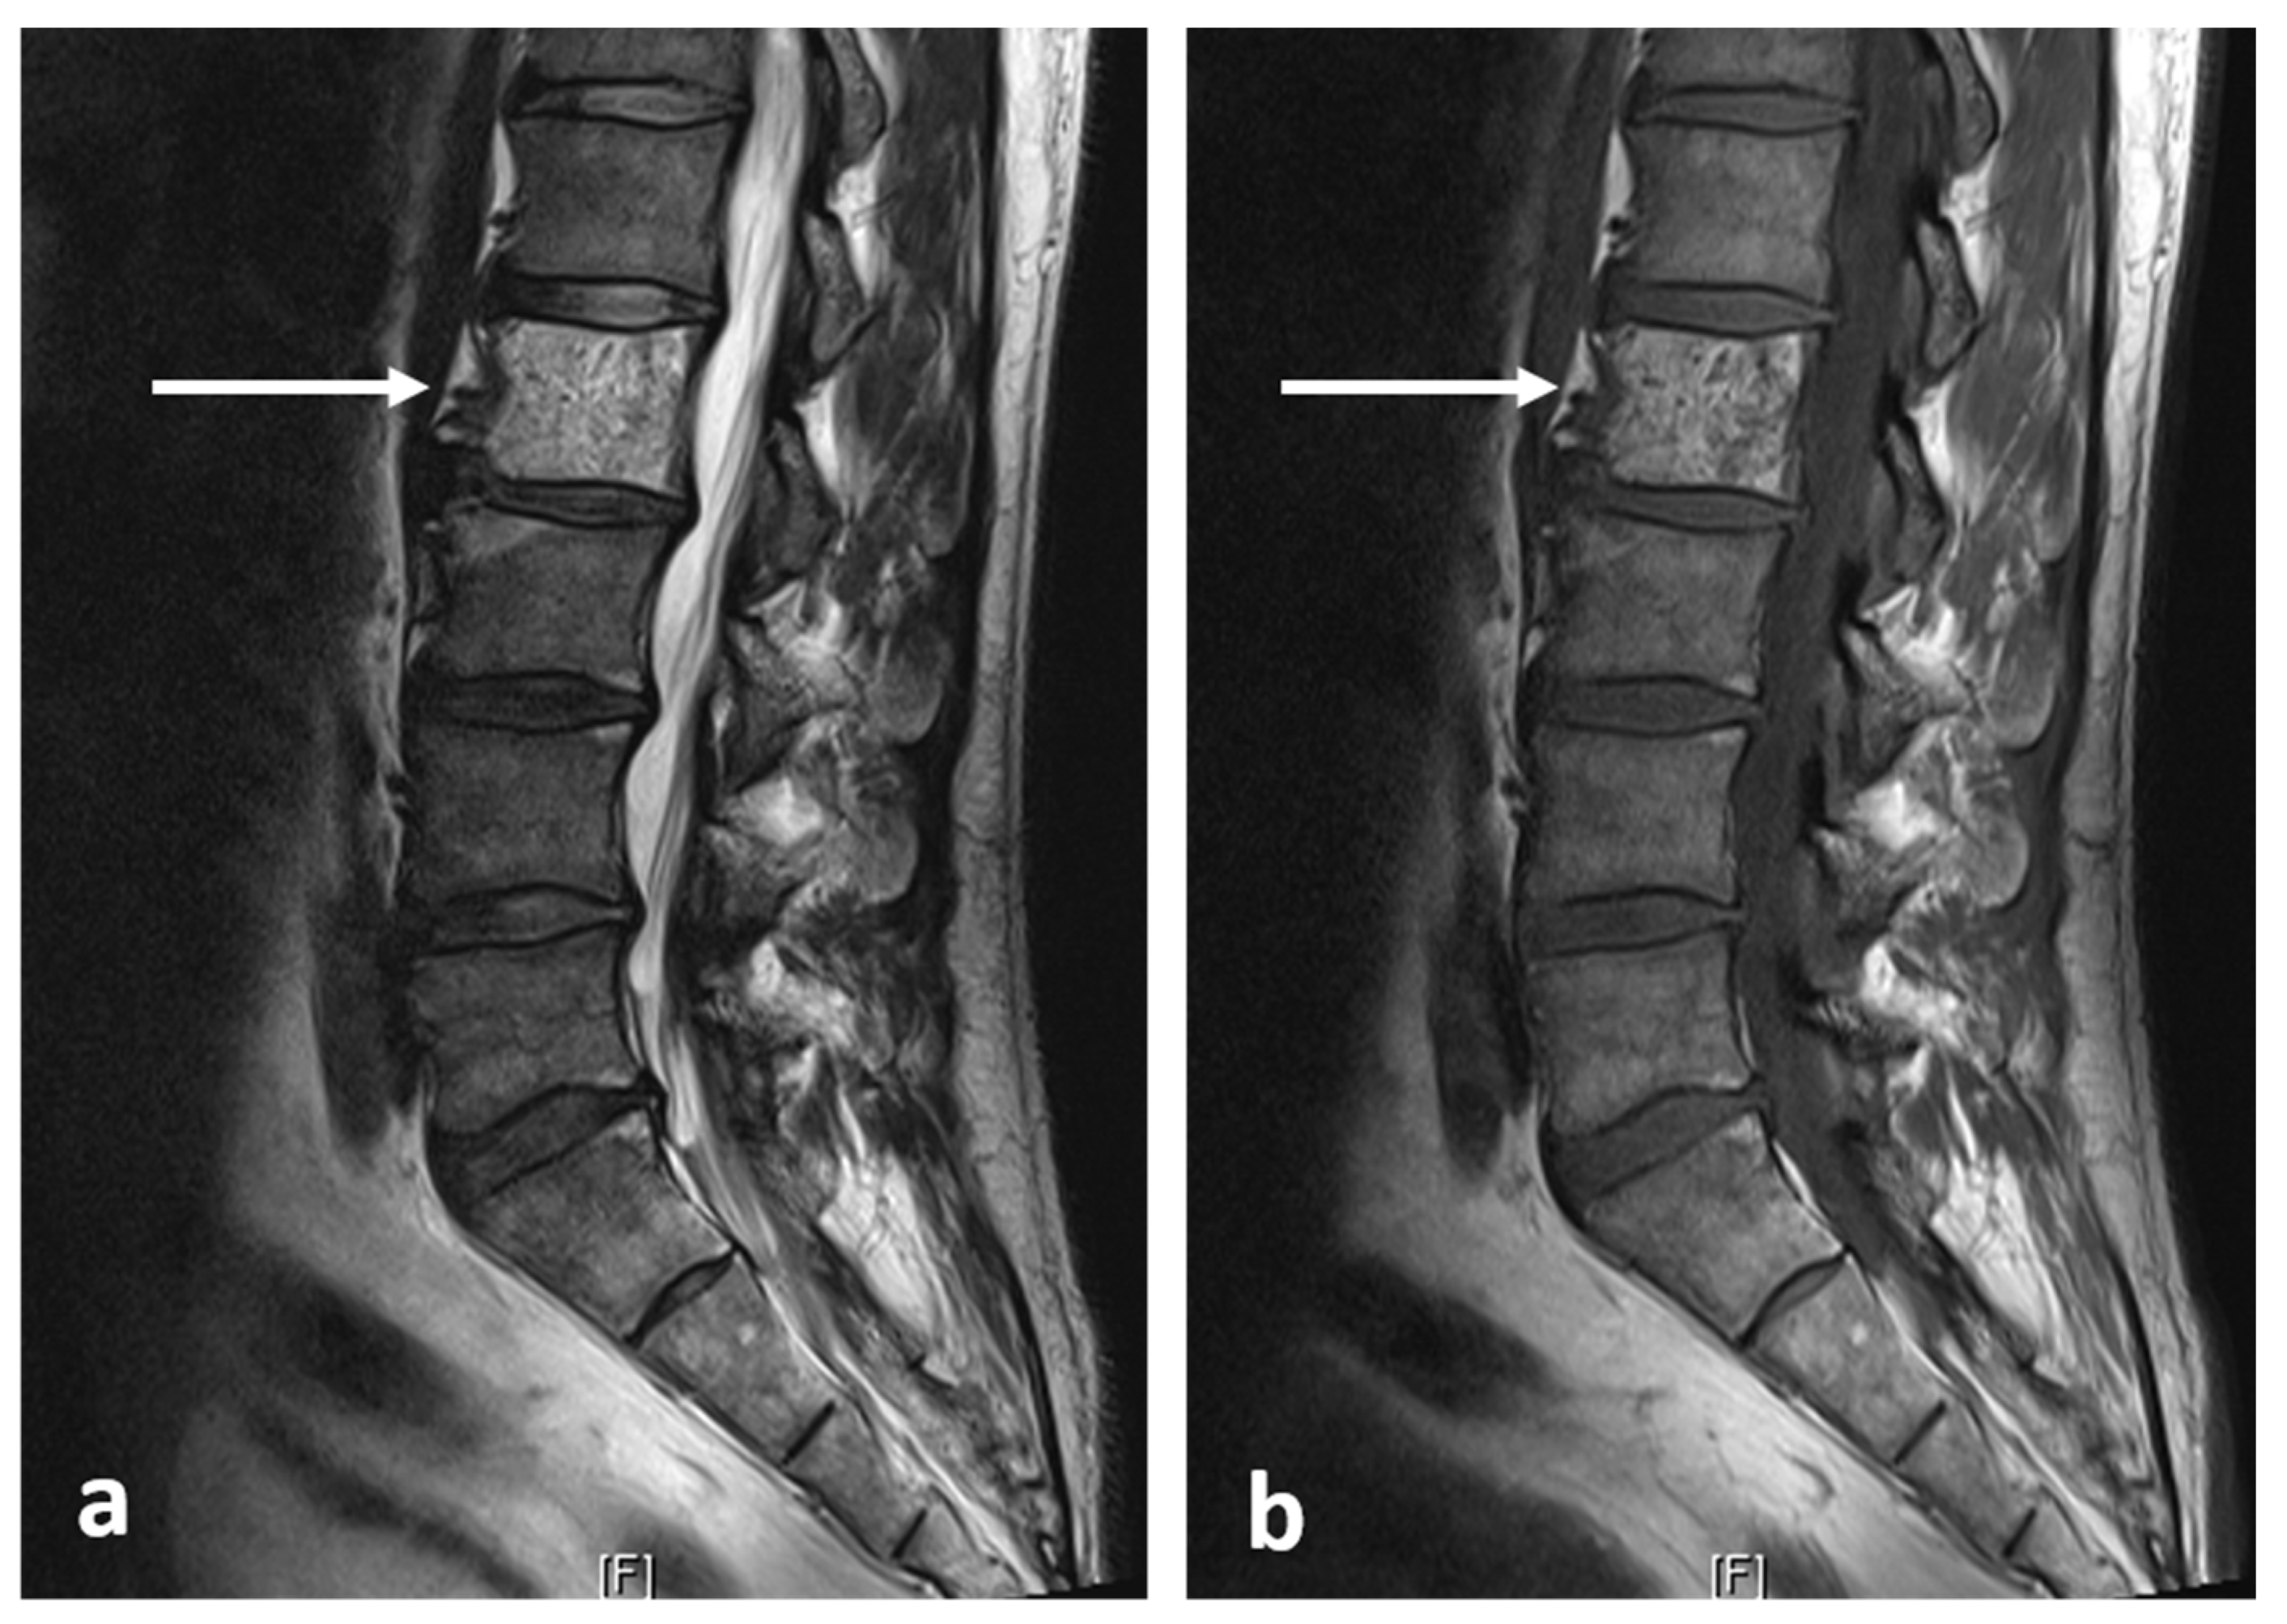

| Osteoid osteoma | Lucent nidus, usually 2–10 mm. May be surrounded by sclerotic rim. | Surrounding marrow oedema on fluid sensitive sequences (best seen on STIR). Nidus can be occult on MRI. |

| Osteoblastoma | Expansile lucent lesion. Sclerotic rim. Bone destruction. Variable intralesional ossification. | Low to intermediate T1 signal and intermediate to high T2 signal. Surrounding soft tissue oedema, extra osseous soft tissue component. |